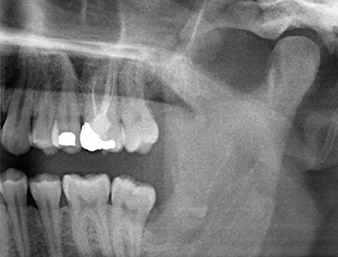

A 26-year old patient had recurring pain in the operative area six months after osteotomy of tooth 38 (LL8) and complained of hyposensitivity in the area innervated by the inferior alveolar nerve. He was referred by the referring dentist, who had not performed the original tooth extraction himself, to the Department of Oral Surgery at the University Dental Clinic Vienna.

The root remnant in the region of tooth 38 (LL8) was already displaying close proximity to the inferior alveolar nerve on the OPG. The root had fractured during the osteotomy but had not been removed by the primary treatment provider due to intraoperative pain. To ensure as little trauma as possible to the tissue, the new osteotomy was to be carried out using a piezo surgical system. The patient had an unremarkable medical history and was a non-smoker.

OPG 6 months after osteotomy

Fig. 1: OPG 6 months after osteotomy of tooth 38 (LL8): radix relicta lies close to the inferior alveolar nerve.